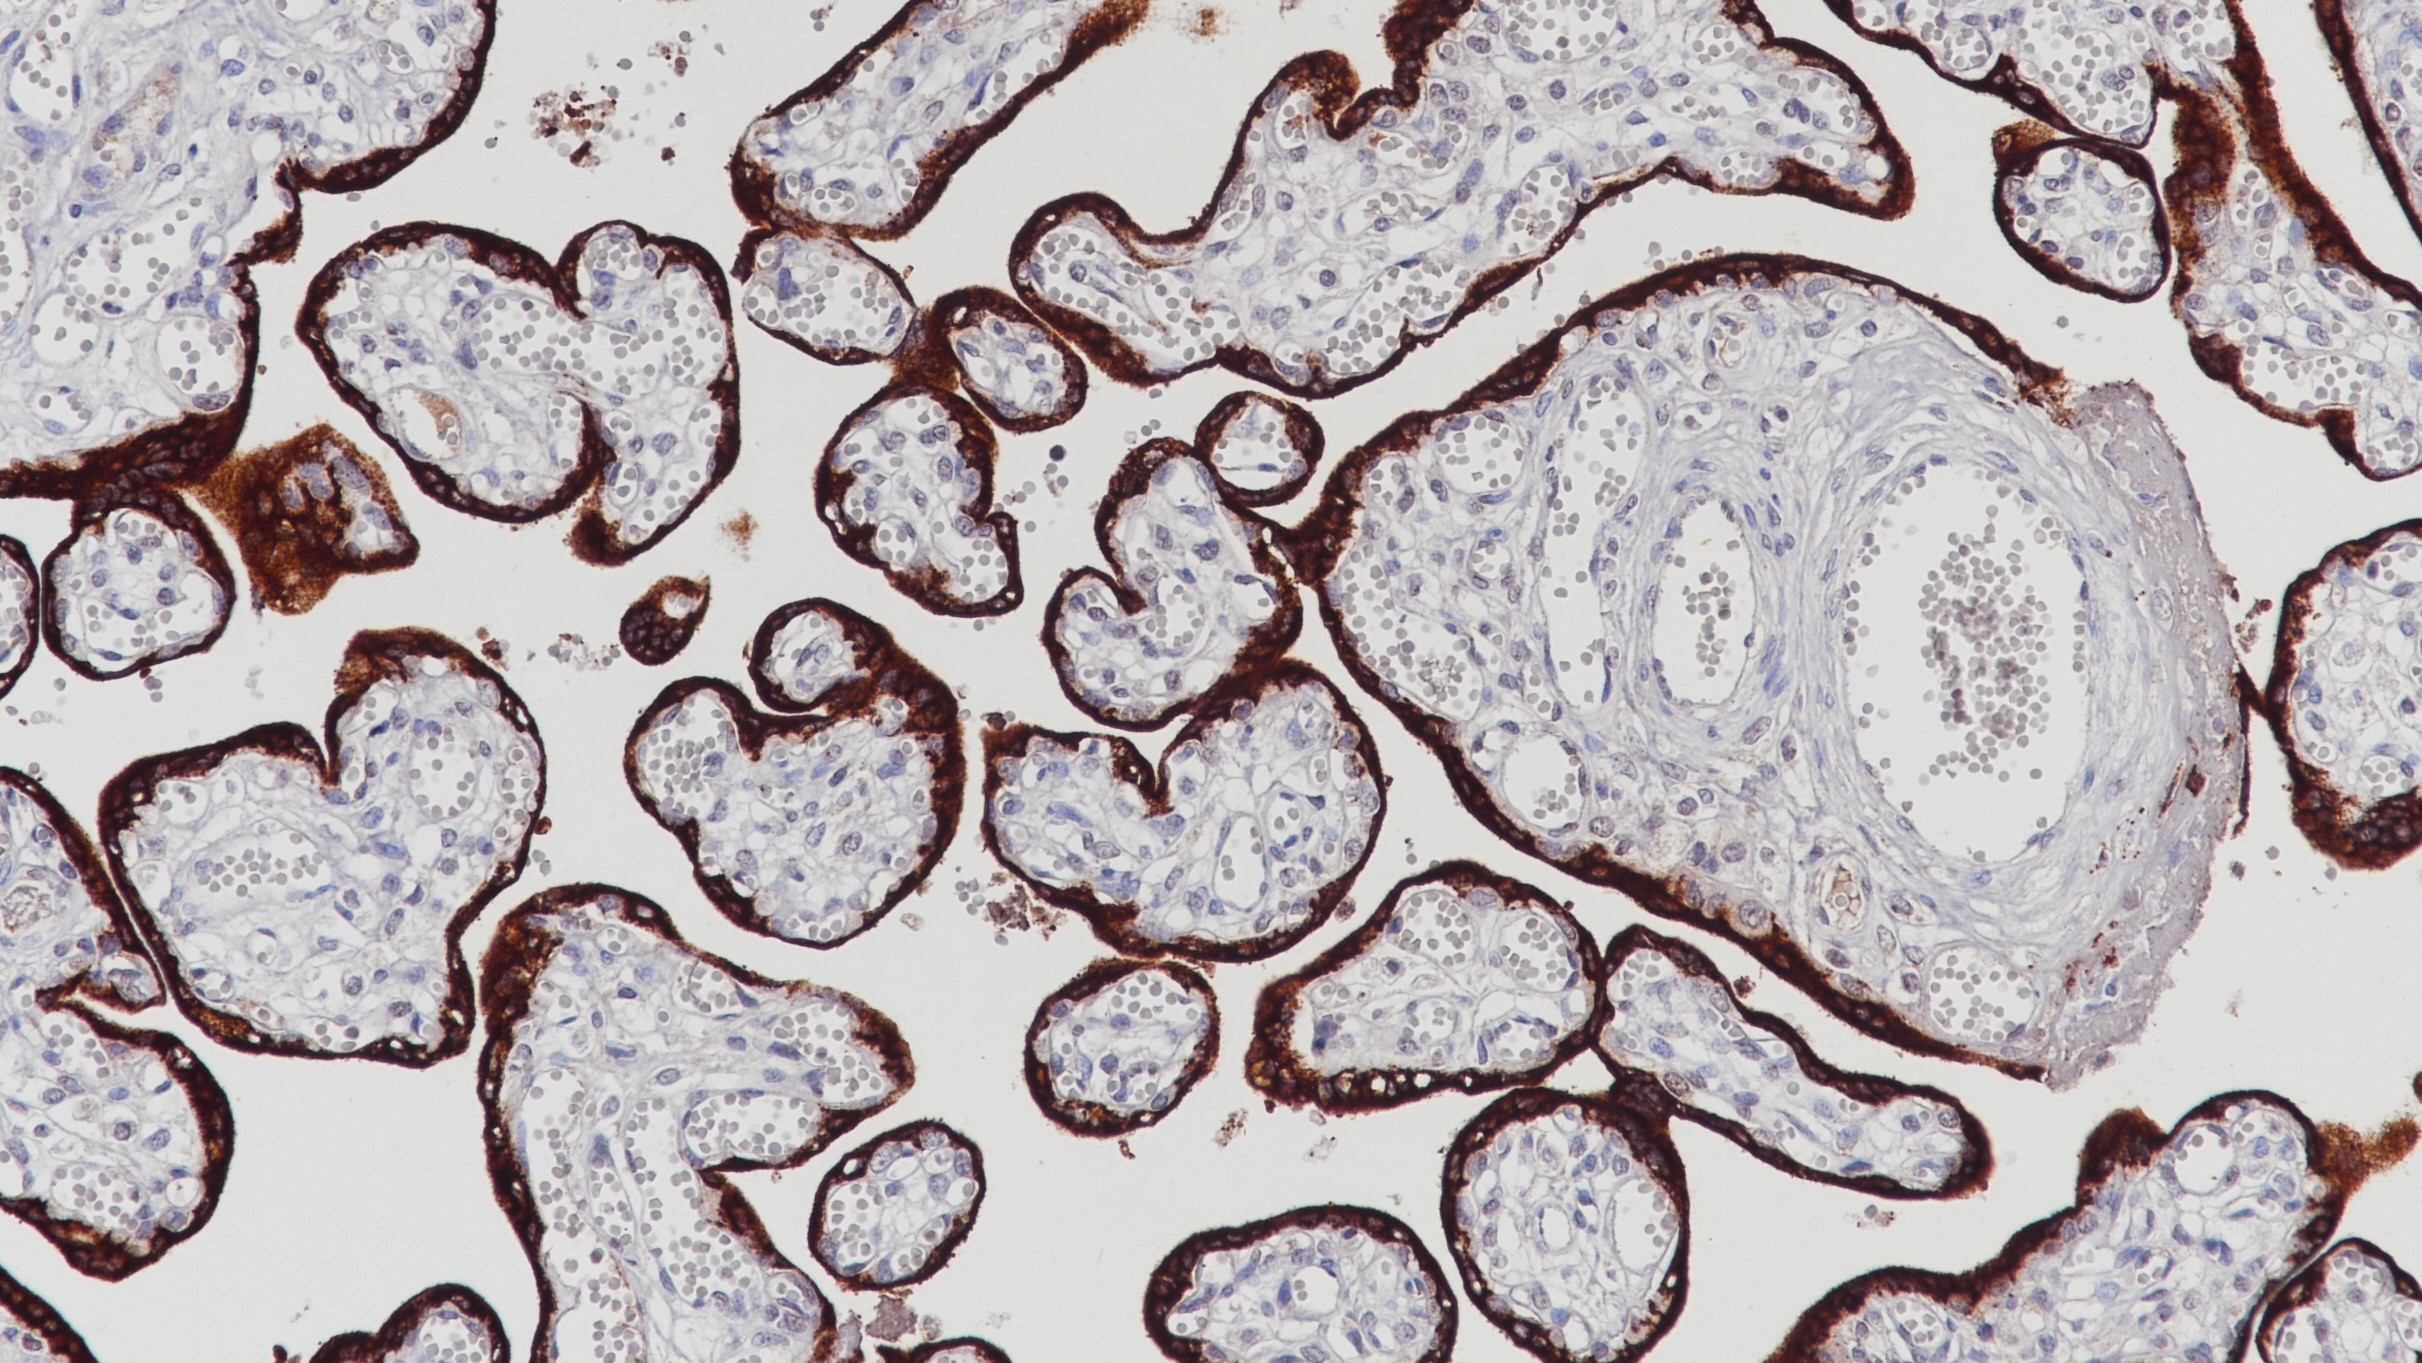

1.Singer, W, Spellacy, W.N. HUMAN PLACENTAL LACTOGEN. British Medical Journal 20 September 1969 668-669.

2.C W Welsch, M J McManus. Stimulation of DNA synthesis by human placental lactogen or insulin in organ cultures of benign human breast tumors. Cancer Research 37, 2257-2261, July 1977.